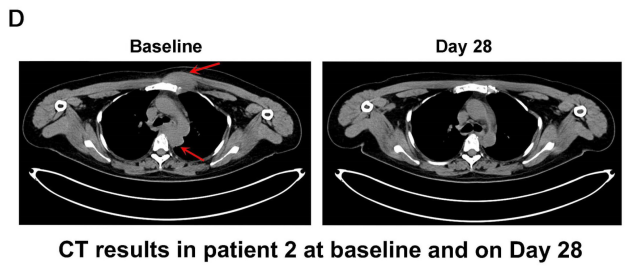

结果显示:接受ESO-T01治疗后,患者疗效显著。患者1在治疗第2个月达到严格意义上的完全缓解(CR),所有髓内和髓外病变均消退(详见下图B);患者2在第28天达到严格完全缓解,病变完全消退(详见下图D);患者3和4达到部分缓解(PR),至第28天肿瘤病变缩小,骨髓中微小残留病灶转阴。

▲图源“Lancet”,版权归原作者所有,如无意中侵犯了知识产权,请联系我们删除